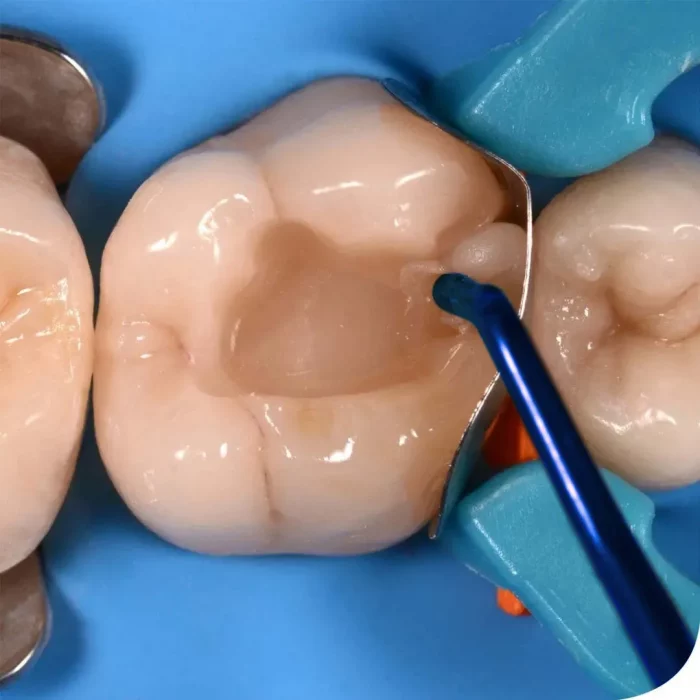

- These instruments help the dentist to insert, sculpt, and contour dental composites with complete ease.

GDC uses the finest material, the best grade of stainless steel, depending upon the type of instruments; various quality checks are made starting from the selection of the forging to the final approval by the quality control department. Used in any common obturation technique for finishing the margins of plastic filling restorations. The titanium coating of instruments minimizes the adhesion of the composite.